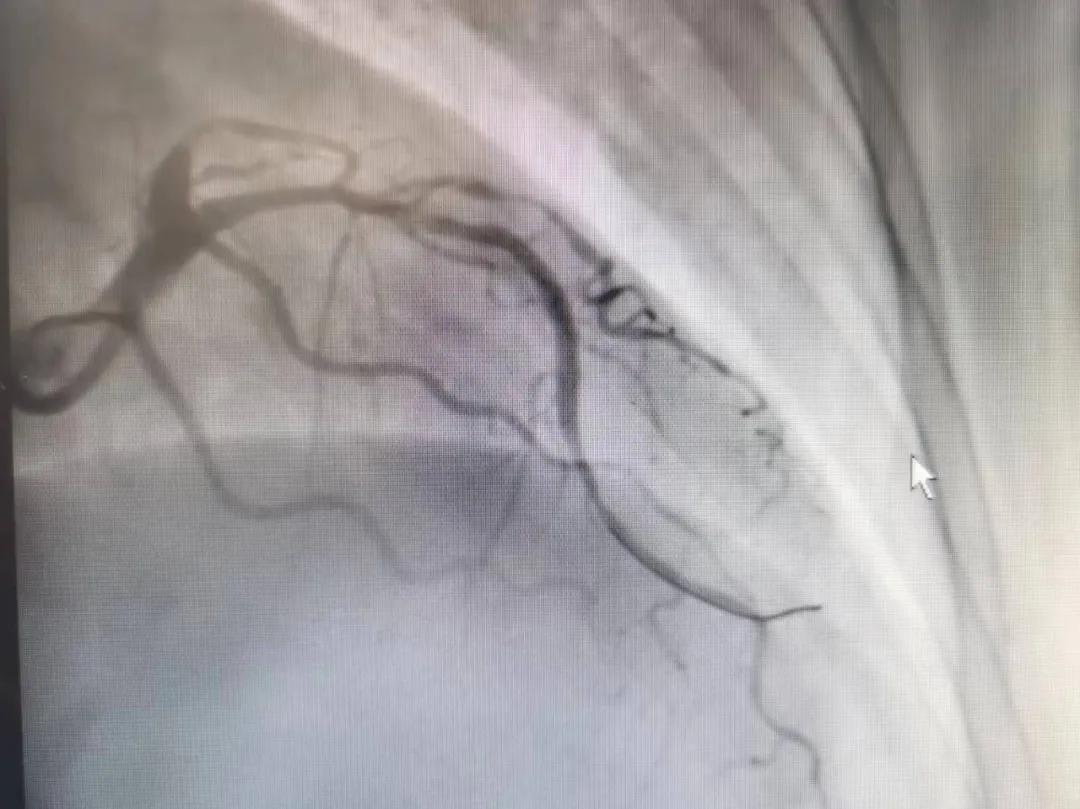

王瑾院長和李慧新主任帶領(lǐng)介入團隊充分評估,決定行前降支冠狀動脈鈣化病變旋磨術(shù),術(shù)中應(yīng)用1.5mm旋磨頭,以15萬-17萬轉(zhuǎn)/分速度共對病變旋磨3次,累計旋磨時間60秒,后復查造影示鈣化明顯減輕,為后續(xù)操作創(chuàng)造了良好條件,隨后應(yīng)用預擴張球囊、切割球囊再次處理病變,并順利植入支架1枚,復查造影顯示支架膨脹及貼壁良好,無夾層、血腫、慢血流等情況,手術(shù)順利完成。患者術(shù)后無不適,胸悶、胸痛癥狀明顯緩解,順利出院。

術(shù)后